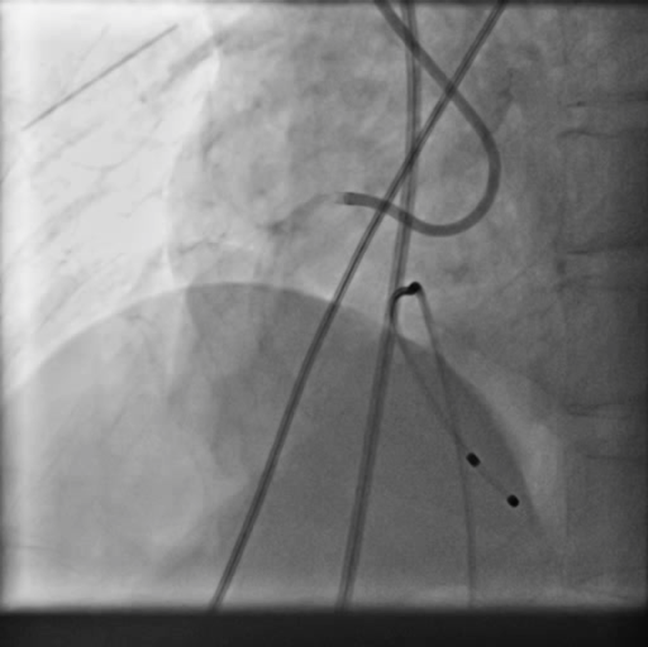

PCIof right coronary artery was initiated on IABP support with amplatz left1 guided catheter and vessel was crossed with great difficulty in repeatedattempts by fielder XT followed by GAIA 2 wire over corsair microcatheter. Microcathetercould not be crossed beyond mid segment calcified CTO, so balloon dilation with0.75 mm balloon was done after which again microcatheter could not be trackedbeyond mid part. Butwe were able to exchange wire to allstar followed by rotawire byplacing microcatheter in mid segment after balloon dilation by 0.75 mm balloon. Rotablation wasdone with 1.25 mm burr at 1,60,00 rpm repeatedly from proximal to mid distalpart. Lesionstill looked unprepared as repeated postdilation with2.25*15 mm followed by 2.5*15 mm non compliant balloon at high pressures showedunexpanded balloon. Againlesion preparation was done with 2.5*15 mm wolverine cutting balloon repeatedlyat high pressures which led to adequate luminal gain and calcium cracks as seenon IVUS run. AfterIVUS run again high pressure balloon dilation was done with wolverine 2.5*15 mmballoon followed by 2.5*12 mm non compliant balloon at 28 atm toadequately prepare the lesion before stent deployment. Stentingwas done with 2.5*32 mm DES, 2.75*32 mm DES, and 3*24 mm DES from distal toproximal in overlapping fashion. Thenfinally high pressure post dilation was done with 2.75*15 mm followed by 3*15mm non compliant balloon and adequate stent expansion was achieved with TIMI 3 flow.